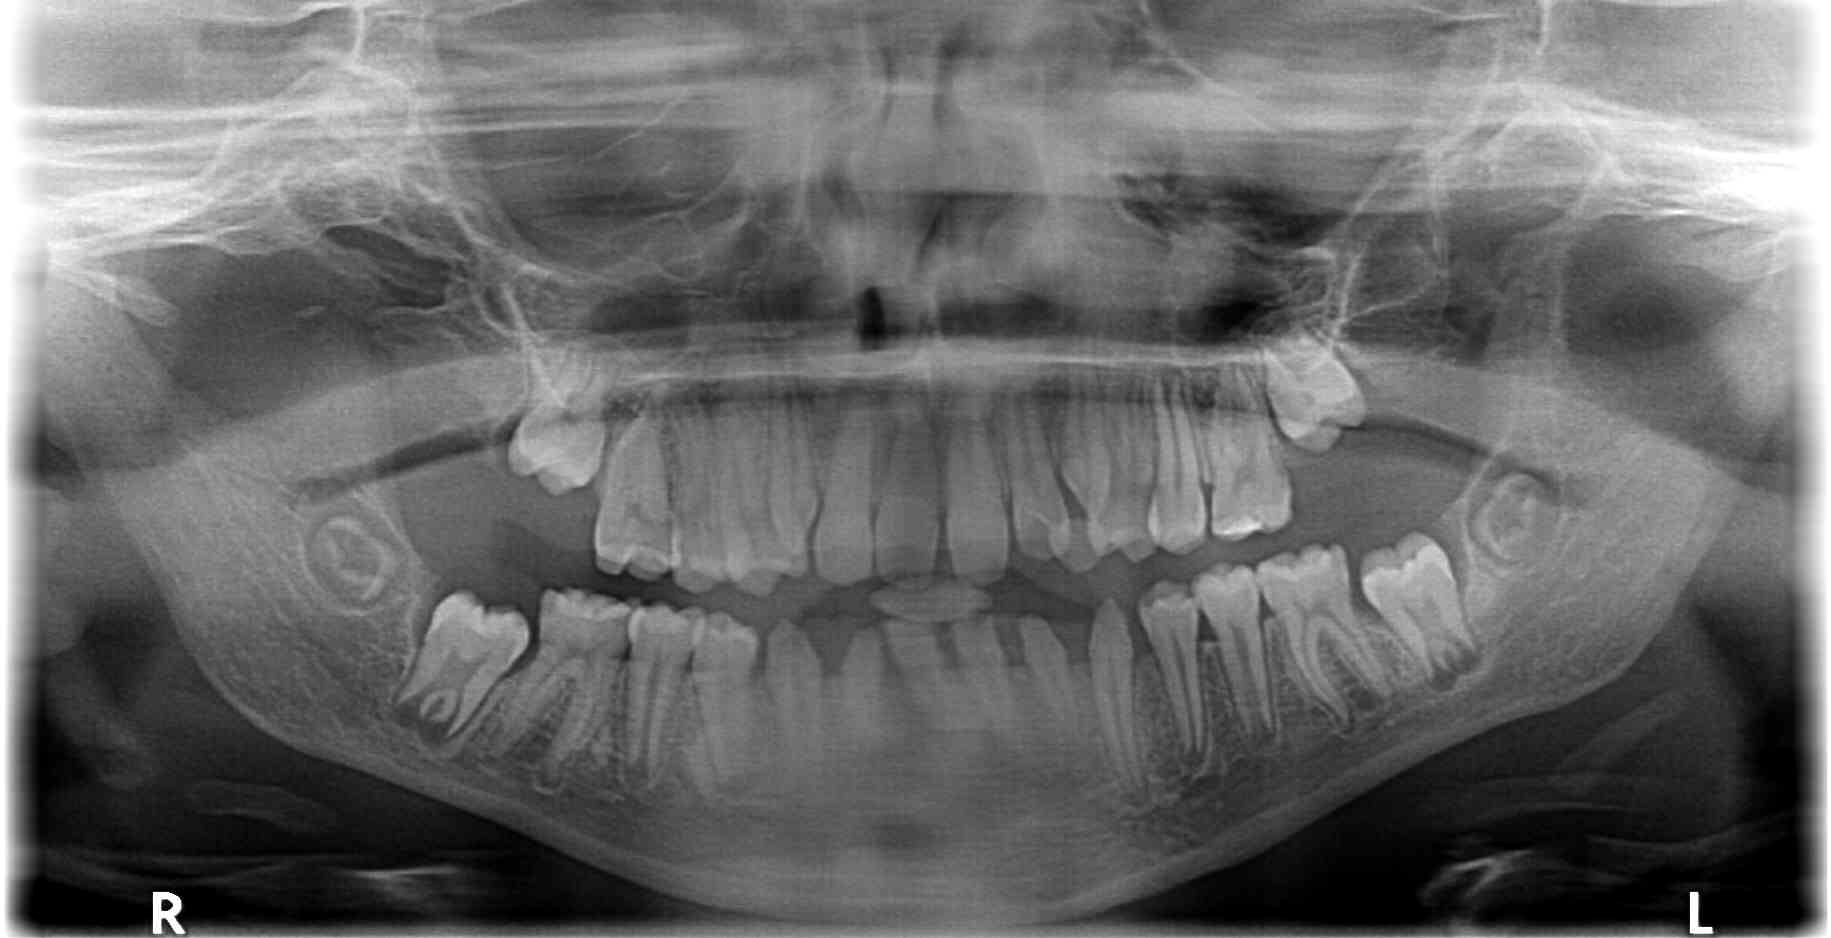

The first signs of dental developmental disorders can be expected after 1-2 years of cancer treatment and they are visible on X-ray images [15] (Figure 2). Cancer treatment leads to changes in the shape, size of crowns and roots, degree of mineralization, enamel and dentin structure with frequent dental aplasia, therefore [1, 4, 6, 11, 15] hypodontia, microdontia, enamel hypoplasia and developmental root defects are typically observed [1, 4, 6, 11, 15]. Staining, discoloration and grooves on tooth crowns are often present [7, 10]. The tooth eruption process is also affected (often due to root development issues), leading to occlusal disturbances [2, 15]. Delays in primary tooth shedding and in permanent tooth replacement are frequent outcomes [3, 6-8].

Figure 2. Panoramic radiograph of a 12-year-old girl treated for a malignant eye tumour with chemotherapy from 5 weeks of age to 6 months of age. Visible V-shaped roots of teeth 16 and 26, reduced conical crowns of teeth 32 and 42 and root shortening of the lower incisors